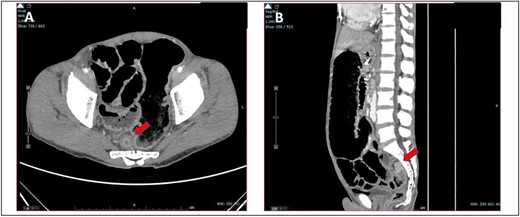

She was presented with an umbilical swelling for the past 1 week which had become painful for the past 2 days, associated with vomiting and unable to pass flatus and bowel motion. On examination, her vitals were normal. Per abdomen, there was 4 × 4 cm swelling at umbilicus with redness and skin changes. Plain abdominal radiograph showed dilated small bowel (Fig. 4A). Her blood parameters showed leukocytosis with white cell counts of 20, haemoglobin of 15, acute kidney injury with urea of 17, and creatinine of 154. Arterial blood gas was normal and no acidosis. The provisional diagnosis was strangulated paraumbilical hernia.

(A) Plain abdominal radiograph showed dilated small bowel (B) intraoperative finding of unhealthy sloughy small bowel segment in the hernia sac and pus was present.

We discussed with patient and her relative regarding the option of anaesthesia either local or general anaesthesia. They agreed and consented for local anaesthesia since it has the least complications and aware of conversion to general anaesthesia if the former method failed to work. We proceeded with the surgery under local anaesthesia and monitored sedation with the help of an anaesthesiologist. We did an infraumbilical transverse incision over the hernia and found small bowel ischemia within the hernia sac with pus (Fig. 4B). The hernia defect was 3 × 3 cm. Ten centimeters of segment small bowel was resected with primary side to side bowel anastomosis using linear stapler 75 mm. The hernia defect is primarily closed with nonabsorbable polypropylene suture. The skin was left open for wound dressing. She recovered slowly from surgery and was able to go home on Day 7 post-operation.